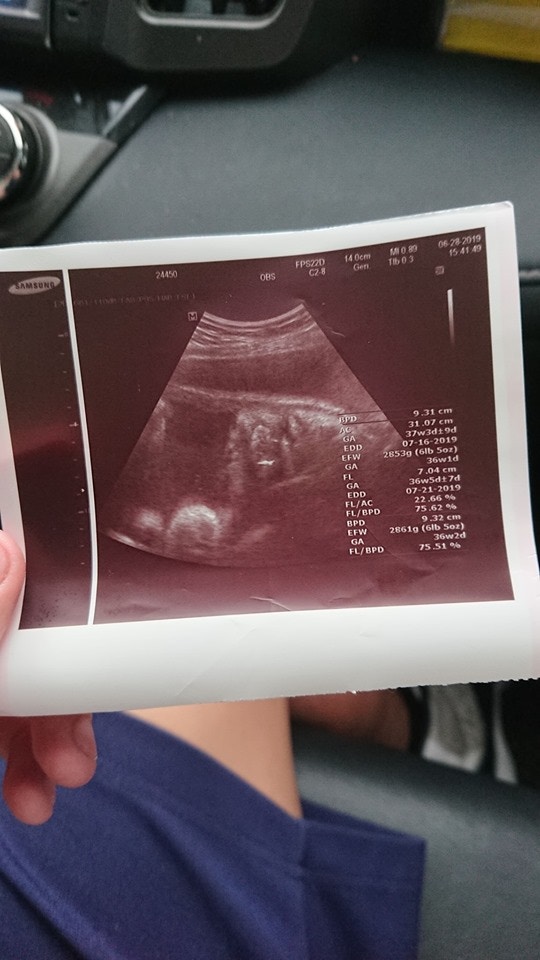

▼原來當時只有高一的兒子,不小心讓女友懷孕了之後,做了產檢才知道胎兒竟然已經37週了!後來原po的老婆終於告訴原po「你兒子讓女朋友懷孕了」,讓原po嚇得傻眼大罵「不是早就警告他不要發生這種事了嗎?」

▼於是他們將女方接回家待產,也帶她做了產科產假、超聲波,想不到4天後寶寶就出生了,讓原po超無奈「兒子竟然只給我4天做心理準備!」